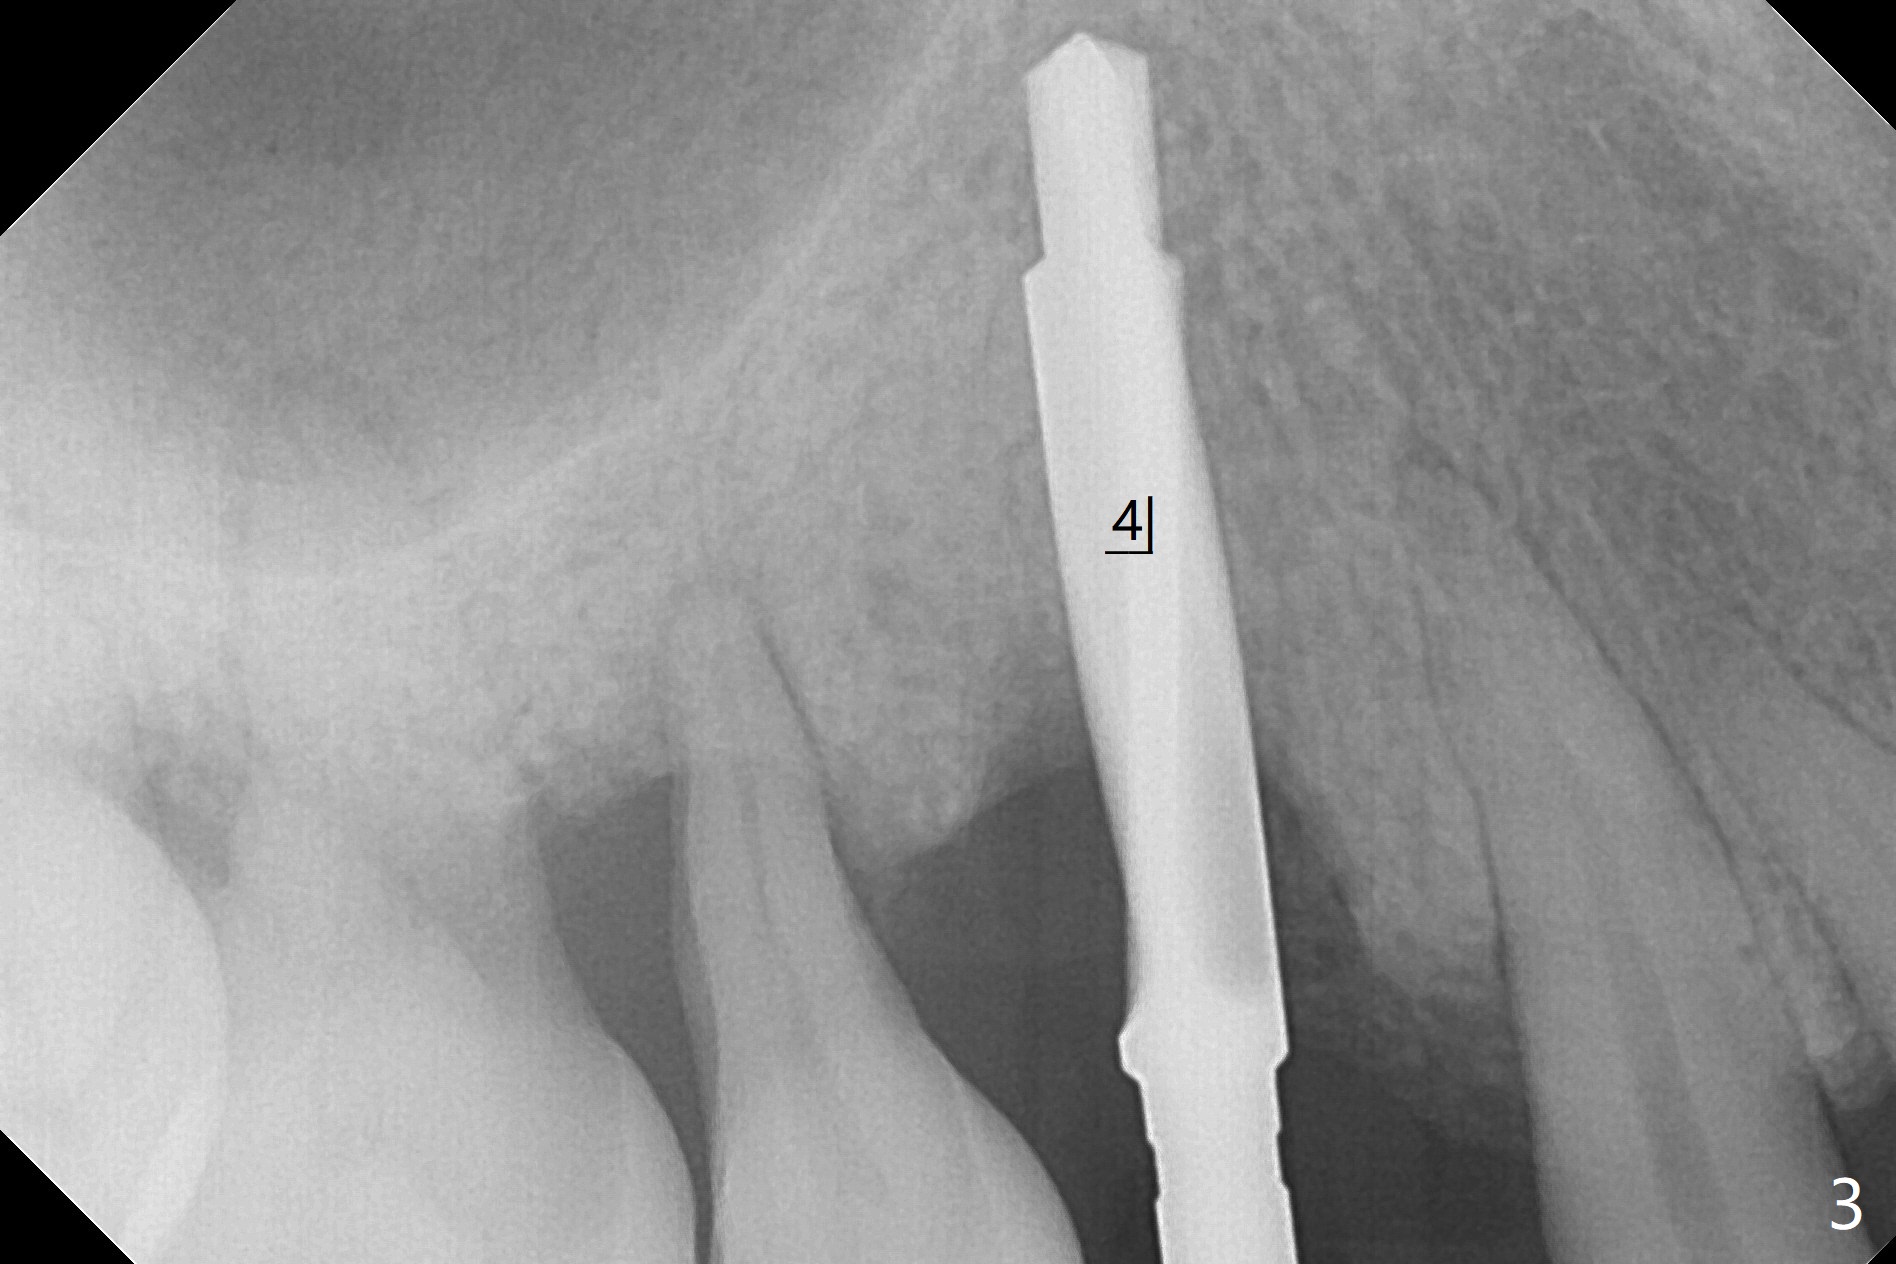

术前CT显示右上4牙槽骨比5窄(图一,二),3.5毫米植体比较合适,况且牙龈厚,基台长的一段式植体显得得当。为了取得最好的植体方位,4先拔除(图三),种植(图四),调整后者深度后,拔除5(术前征求病人同意),开始钻洞(图五),完成种植(图六)。粘性骨粉不仅放置于植体周围,而且6牙根近中(图七),4/5牙槽嵴和龈乳头(P)之间,减少术后龈乳头萎缩(图八:*)。制作两个分开临时牙冠,有利于维持龈乳头。对于病人来说,临时牙冠帮助咀嚼,而对侧拔牙创无法吃饭。术后3个月两个分开临时牙冠(其中一个龈方移位(图九:箭头)保持龈乳头(*)和牙龈外形(图十:*)。临时牙冠取出后,调整基台高度,少量钛屑(不妨大局)附着在健康的牙龈沟(图十一),再次显示两个基台之间龈乳头(图十二:*),衬里,修整的临时牙冠又插回牙龈沟(图十三:箭头),继续维持软组织形态,准备一个月后,调整基台边缘(图十二:箭头),取模。术后五个月大部分骨粉依然保留在植体和邻牙周围,龈乳头退缩不多(图十四: P)。三个月后(术后六个月)钛削无影无踪(图十五,与图十一对比))。永久性牙冠周围空间慢慢会消失(图十六,使用临时性胶水)。